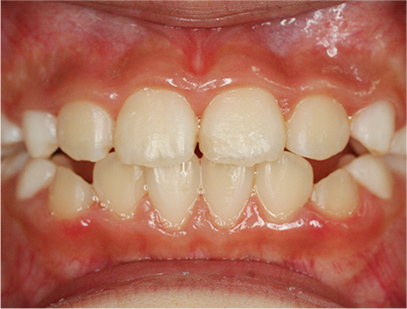

前歯部の開咬とデコボコ

前歯部が咬んでいないことを主訴として来院されました。精査、診断の結果「前歯部にデコボコを伴う開咬」と診断されました。

治療後

• 正面

治療期間は、患者様の努力とお母さまの協力が得られて1年間で終了しました。